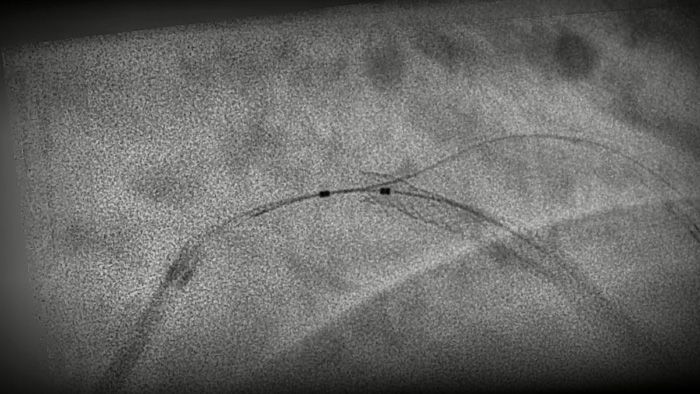

Una tecnología exclusiva de Philips, crea una vista en tiempo real de las arterias coronarias compensada por el movimiento. Un angiograma coronario resaltado se superpone sobre una imagen fluoroscópica 2D en vivo, y crea una hoja de ruta coloreada que se ajusta automáticamente, proporciona retroalimentación visual continua sobre el posicionamiento de cables y catéteres.

StentBoost Live10 le ayuda rápidamente a verificar el posicionamiento antes y después de desplegar balones, stents y dispositivos intracoronarios para ver la implementación y confirmar la expansión completa. Y todo ello se realiza en tiempo real, por lo que ya no tendrá que esperar a recibir nuevas imágenes antes de reposicionar.